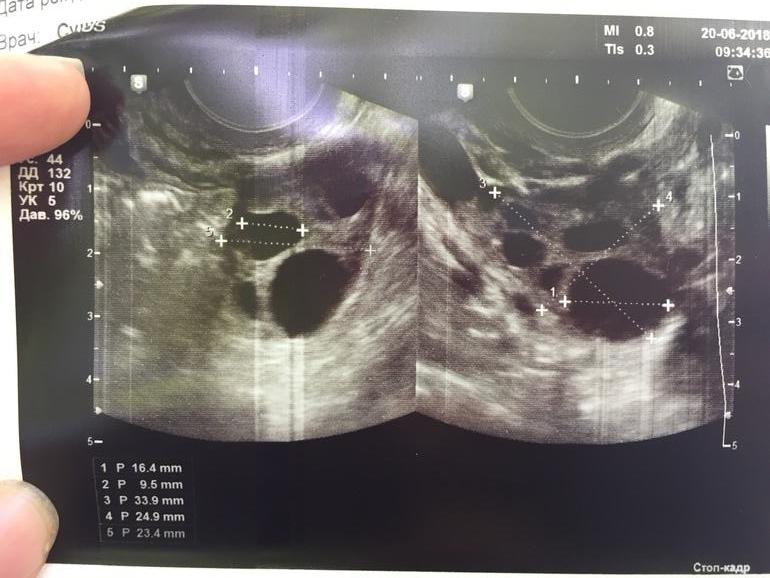

Хожу в основном в одно и тоже место, там аппарат хороший и врач.. но попала сегодня на другого врача, и она не знает!! Говорит, что О была, потому что у правого Я есть жидкость, но ЖТ не видит 😄🤷♀️ возможно типа ещё не образовалось, или не видно из-за еще одного ДФ 17мм.. или это вообще тот же фолликул, что и на 14дц был🤦🏼♀️ Та же история с ЛЯ.. но там вроде все-таки ЖТ есть, и то не факт😂

Вот теперь сижу, гадаю...) жду протокол)) по сути.. от укола 10000 фолликулы же не могли остановиться/уменьшиться.. они либо в кисту бы уже ушли, либо лопнули. Но кист нет, и нет ЖТ.. есть 2 ДФ в каждом Я. Узист даже не стала писать в заключении.